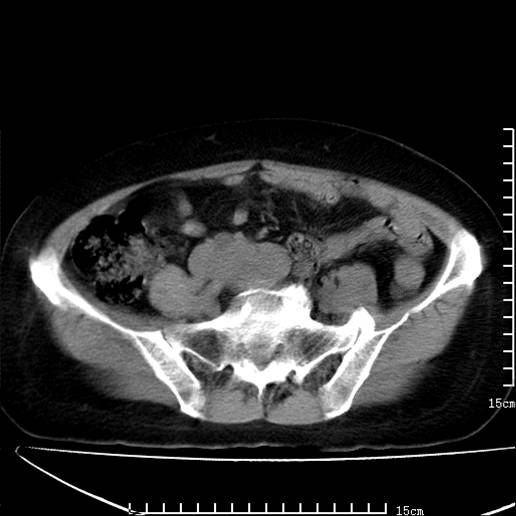

以下是引用pujunzhi在2008-5-30 15:31:00的发言:[br]异位肾—盆腔肾。当看到肾窝无肾脏时,要想到孤立肾和异位肾,异位肾最常见是盆腔肾,偶见胸腔,易误认为肺占位,只要想到就不会漏诊。建议增强扫描。